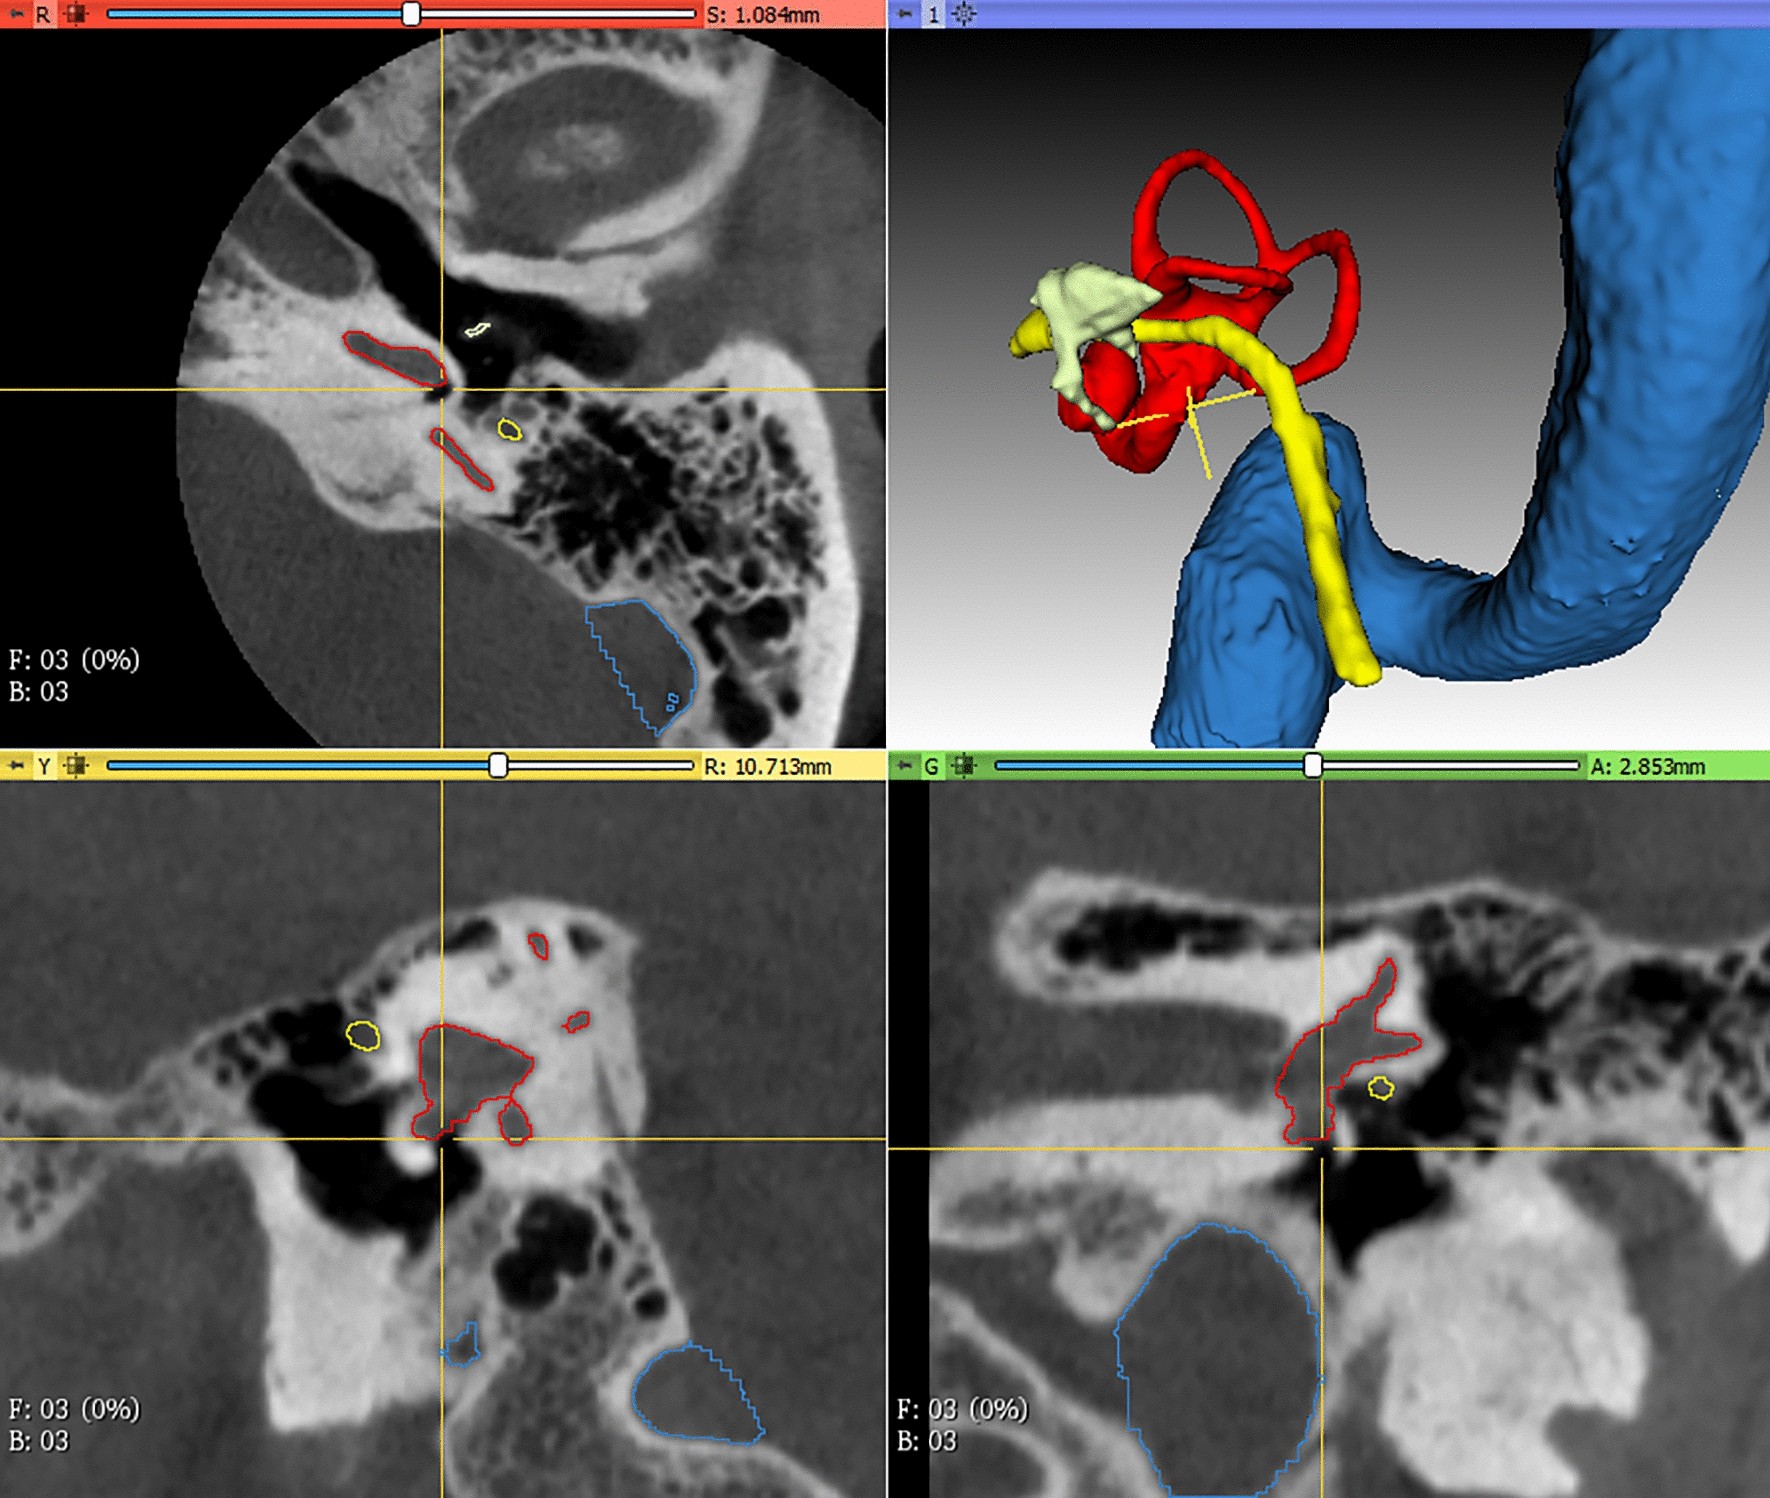

A CT temporal bone scan is a specialized imaging procedure that focuses on the temporal bones, which are located at the sides of the skull and house the structures of the inner ear and the auditory system. This scan uses advanced computed tomography technology to provide detailed cross-sectional images of the temporal bone region, including the inner ear, middle ear, and the surrounding structures.

The primary purpose of a CT temporal bone scan is to evaluate conditions affecting the ear and surrounding areas. It is commonly used to diagnose and assess various disorders such as chronic ear infections, congenital abnormalities, bone erosion, and tumors of the ear. The scan can also be instrumental in planning surgical interventions, such as ear surgery or cochlear implants, by providing precise anatomical details.

A CT temporal bone scan is utilized for a variety of diagnostic and evaluative purposes. It is particularly useful for examining the structures of the ear, including the middle and inner ear, and the surrounding temporal bone area. This scan is commonly used to diagnose and assess chronic ear infections that may have led to bone erosion or other complications. It is also valuable in identifying congenital abnormalities of the ear and related structures, which may affect hearing or balance.

The scan is instrumental in detecting tumors within the temporal bone region, such as acoustic neuromas or other growths that may impact auditory and vestibular functions. Additionally, a CT temporal bone scan can provide essential information for planning and guiding surgical procedures, such as ear surgery, cochlear implants, or reconstructive surgeries. It helps surgeons by offering a detailed view of the anatomical structures, aiding in the precise placement of implants or the removal of tumors.

In cases of trauma, the scan can assess damage to the temporal bone and its components, including fractures or dislocations that might affect hearing or balance. Overall, the CT temporal bone scan provides critical insights into a range of conditions affecting the ear and surrounding structures, facilitating accurate diagnosis and effective treatment planning.